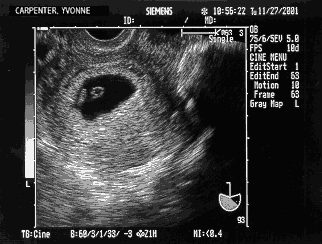

2nd trip to the doctor — November 27th — 6.5 weeks

Baby Carpenter at 6 weeks Matt: Our visit starts out on a bummer note when the doctor’s assistant says, “It looks like your numbers have gone down to 8,100.” My heart, or rather chest, was hit with a surge of adrenalin. Yvonne somehow says “Oh, OK.” Before I can say anything the assistant says, “Oh, I’m so sorry, I put the decimal place in the wrong spot, it is 81,000!” Ok, all is forgiven but that seems like the sort of thing you check before you open the door to tell two people if they are still pregnant or not. The doctor then comes in and all is forgotten because this women is just awesome. The more she talks the more I smile. As luck would have it they are testing a new ultrasound device so off we go. Right there in front of us we see our child’s first heartbeats! I still can’t stop smiling. Of course we ask tons of questions but the main point is we are back on track. Pictured is a scan of the ultrasound of our little embryo. By measuring the CRL (Crown Rump Length) the doctor says our baby is at 6 weeks — right on schedule. Below I enlarged a portion of it and scanned in some photos from a book, A Child is Born, to show what is going on at this time. I should say that there are two dates that get used when talking about a pregnancy. The common one which is the one we are using is the # of weeks since the start of the last “that time of the month” which for us was October 13th. Of course it is impossible to get pregnant at that time and so you end up with books showing pictures with captions like “at 6 weeks the 4 week old embryo” or “4 weeks since conception” etc. trying to account for the approximately 2 week difference. After a while the books then use the more common number as well but in those first weeks obviously 2 weeks can make a big difference. Point is I think I got the right pictures by editing and morphing several different photos that were taken before and after where we are. Oh, by the way, the doctor told us that on her first pregnancy she cut out all soft drinks as well:-) Oh, by the way part 2, it was a blood clot:-)

Baby Carpenter at 6 weeks compared to a book baby Yvonne: Oh-hooo! I got an 81,000!!!!!!! That was only after the nurse got her higher math together, but it was still an 81,000! A minor mistake on her part, but one that could easily have caused a heart attack on a father-to-be. Since I was expecting the worst (darn hereditary pessimism...), I did not get nearly as shocked as Matt did. He looked as if he was about to be hit by a train — sort of that “deer caught in the headlights” look! We later talked to the doctor and she too seemed bothered by the nurse’s mistake. However the good news was so good that we quickly forgot about it and moved on to the room where a new ultrasound machine was going to be demonstrated — and I was going to be the demo subject. It was pretty exciting. The only apprehension on my part was that I was about to get naked in front of a little crowd of doctors and technicians! It was fine after all since there was only one technician present besides my doctor and Matt and the technician was only interested in the ultrasound’s features and not mine. We got our first baby picture for what promises to be a large collection! It was quite impressive to see another heart beating inside me. Somehow it doesn’t sound possible... Oh, by the way part 3, who is still on “pelvic rest,” Mr. Pepsi police????